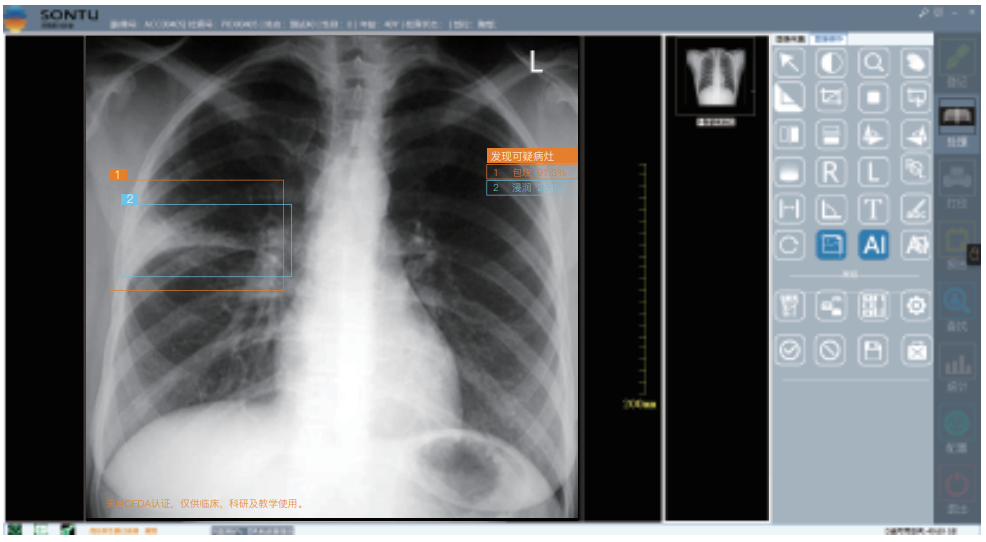

深图软件操作系统:

一键即可完成辅助诊断,定位可疑病变

深图AI辅助诊断系统标注示意:

标注异常位置、呈现病变信息